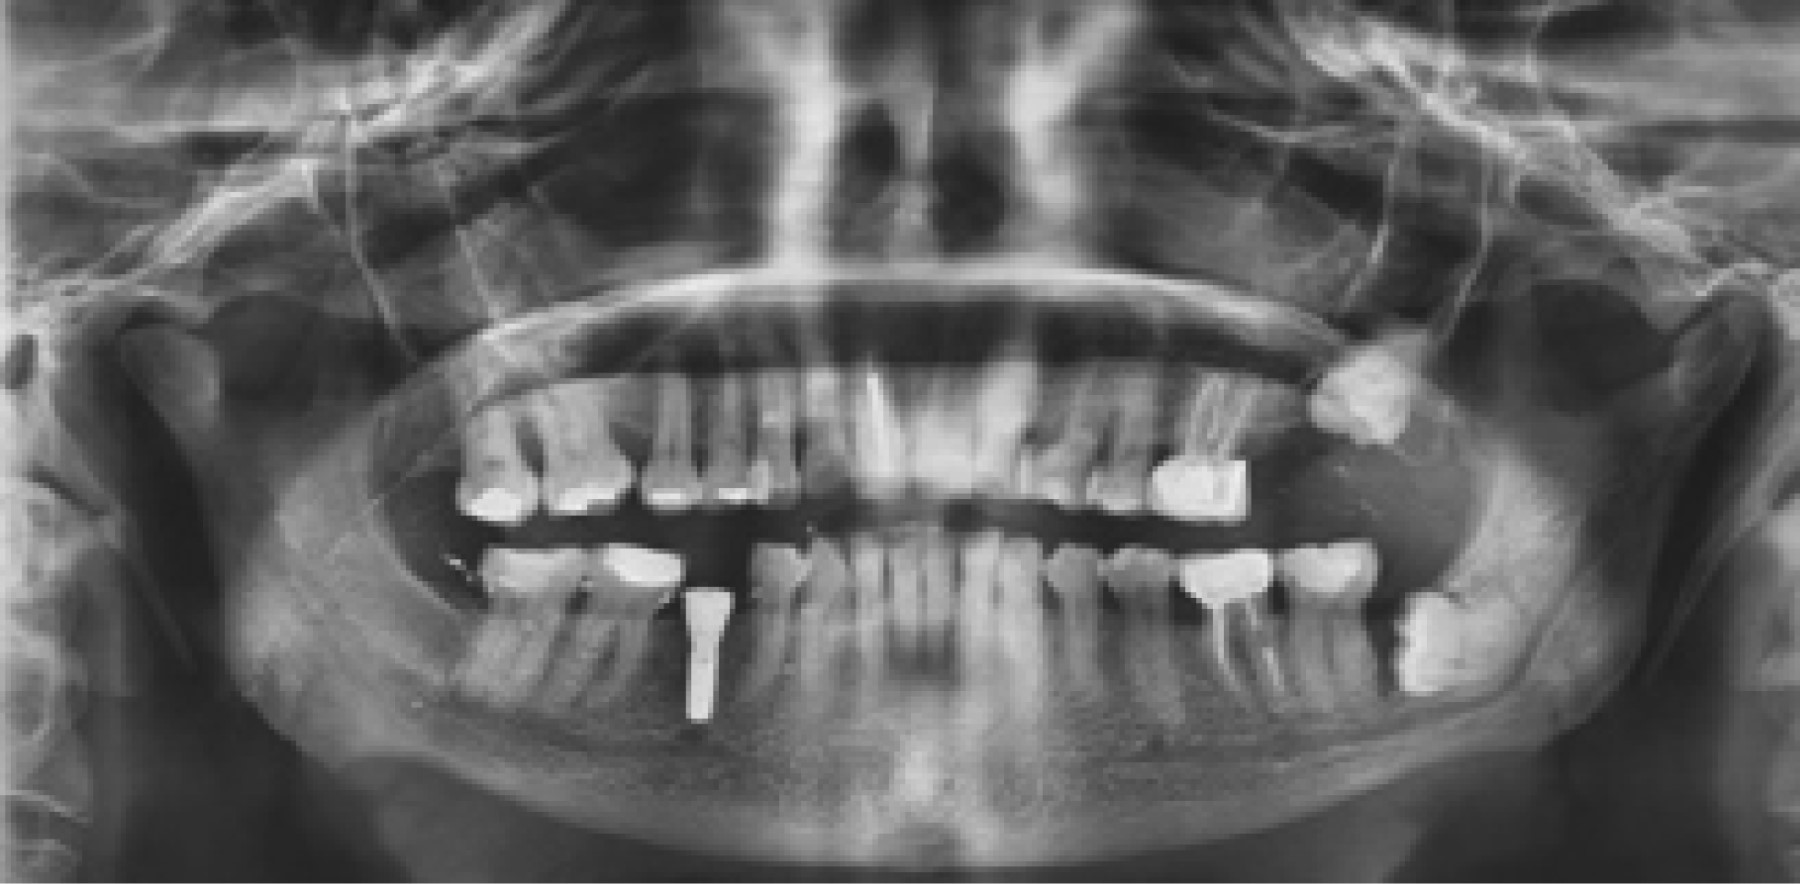

De los 500 pacientes incluidos en este estudio, 336 (67%) pacientes correspondieron al género femenino y 164 (33%) al masculino, con una media de edad de 43 años (mínimo de cinco años y máximo de 91 años con una desviación estándar de 20.7). En 239 (47%) pacientes no se observaron alteraciones. Los principales hallazgos fueron los siguientes: 226 (45%) casos con pérdida ósea de proceso alveolar, seguido de hallazgos radiográficos sugestivos de alteración en la zona articular (ATM) con 171 (34%) casos; en 151 (30%) casos se observaron signos radiográficos de calcificación del ligamento estilohioideo (CLE-síndrome de Eagle) (Figura 1); 18 (3%) casos presentaron estructuras correspondientes a calcificación de carótida (CC) y en 11 (2%) casos se localizaron zonas radiolúcidas semejantes a lesiones quísticas (Figura 2). Los hallazgos se reportan en la Tabla 1.

Respecto a la muestra de CLE (Figura 3), el expediente clínico de 51 pacientes indica que presentaron síntomas relacionados con síndrome de Eagle (SE), mismos que se describen en la Figura 4. Otras de las patologías encontradas fueron las calcificaciones de la carótida en 18 casos (Figura 5), sin que se asociaran con alguna manifestación clínica, o hubieran sido detectadas en el expediente clínico.7,8